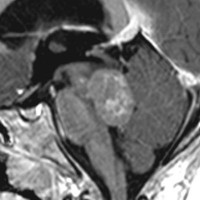

脳幹部から発生した退形成性神経節膠腫 grade 3

軽い右顔面神経麻痺で発症した小児で,右上下肢の軽度の失調症もありました。脳幹部(橋)の右背側から発生した腫瘍で,軽度の閉塞性水頭症を合併しています。左はT2強調画像で,橋の右側ににじむような浸潤像と浮腫があります。腫瘍は小嚢胞を形成してT2強調画像で実質は等信号です。真ん中の画像はCISS画像で橋が腫大しているのがよくわかります。右側はガドリニウム増強像で,全体が増強されてまだらな増強所見となっています。正中後頭下開頭で全摘出 gross total removal して,局所放射線治療とtemozolomide, cisplatine, etoposide, gleevec, hydoreaなどの化学療法を行いましたが,手術後4ヶ月で激しい播種再発を来しました。